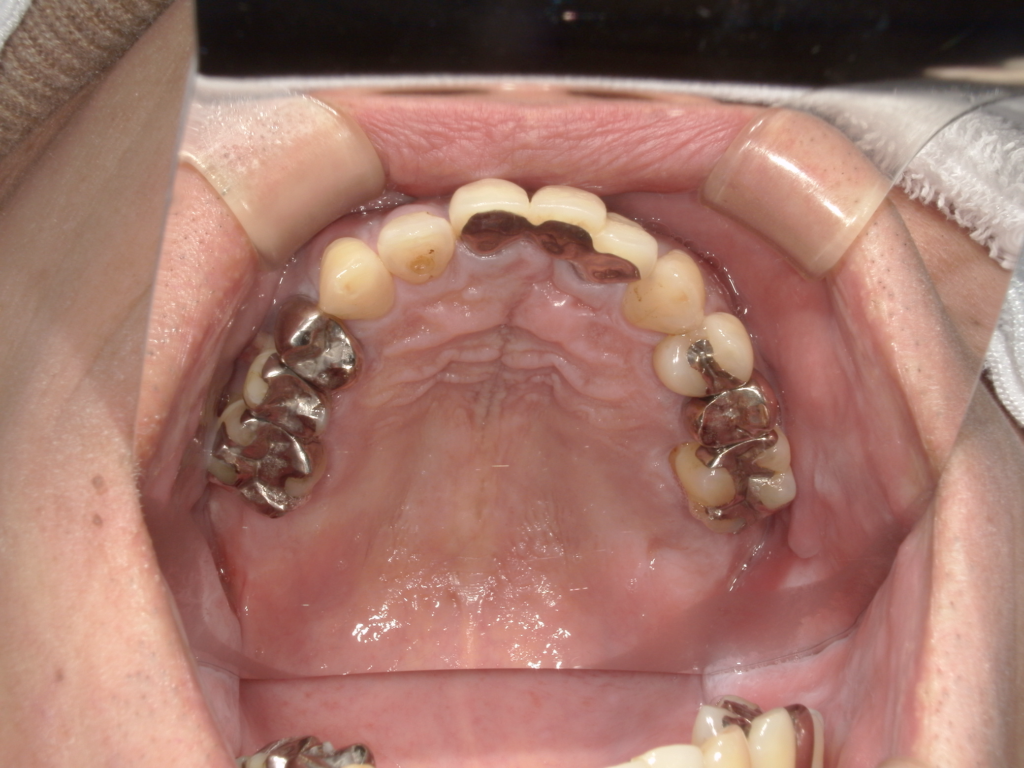

左右の上顎にインプラントを埋入しました。左下にインプラントを埋入しました。上部構造物は、全てセラミックで作ってあります。

治療前

治療後